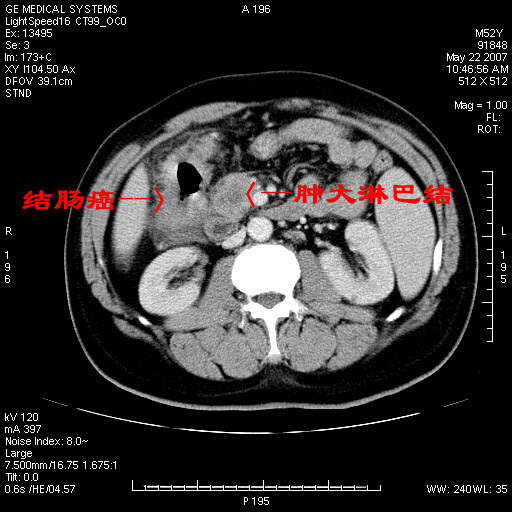

以下是引用余辉在2007-5-22 20:12:00的发言:[br]升结肠管壁明显增厚,增强有静脉期持续增强,结合患者病史,考虑结肠癌可能性大,临近脂肪影密度增高,混浊,恐有肠系膜浸润转移,建议镜检

以下是引用gaoxiao在2007-5-22 20:49:00的发言:[br]考虑升结肠癌向周围侵犯,胰头钩突受侵。

以下是引用dyqct在2007-5-22 20:43:00的发言:[br]支持结肠肝曲占位性病变(浸润型结肠癌可能性大)。胆总管下端扩张,原因待查。

以下是引用蓝宇在2007-5-22 21:29:00的发言:[br]密度不均,考虑结肠癌可能,建议进一步检查